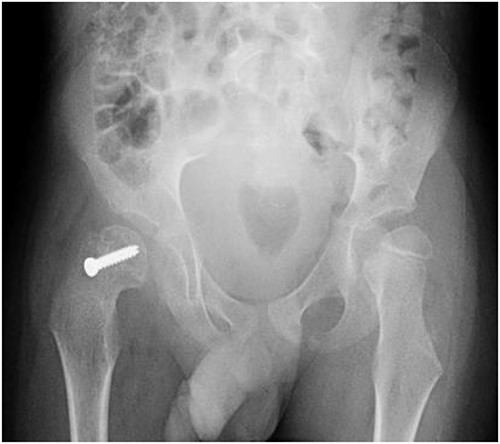

A 5-year-old independent ambulatory Middle Eastern boy with CP who was born preterm and developed grade III intraventricular haemorrhage and periventricular leucomalacia and was on AEDs, including valproic acid (VPA) and levetiracetam (LEV), for >3 years and was controlled over the last year (no history of seizure attack) presented to the emergency room (ER) with right hip pain and inability to bear weight for 4 weeks; the patient had no history of fever or trauma. Physical examination shows a thin, the weight is 12 kg, the height is 101 cm, vital signs within the normal range, tenderness over the right hip, and external rotation of the right hip, with restricted hip mobility. A radiological study was performed ~3 months before the patient presented to the ER for follow-up examination of a left hip coxa valgus deformity with no apparent abnormalities in the right hip (Fig. 1). Initial imaging studies conducted in the ER showed an anterior–posterior view of the pelvic radiograph, revealing Klein’s line [13] not intersecting the capital femoral epiphysis (Fig. 2), and frog-leg lateral view radiograph of the right hip (Fig. 3) confirmed SCFE and Southwick’s slip angle [13] of ~50° (moderate). Laboratory findings were clear for endocrine and renal diseases or infection, except for low vitamin D (total 25-OH Vitamin D: 43.4 nmol/L), suggesting vitamin D insufficiency. The diagnosis was confirmed with clinical and radiological studies as right-sided unstable SCFE requiring surgery. Surgical intervention was performed with percutaneous in situ fixation using a single fully threaded 4.5-mm cannulated screw (Fig. 4). Postsurgical rehabilitation included non-weight-bearing right lower extremities for 6 weeks. Regular follow-up with serial radiology studies showed stable fixation with no migration of screw or further slippage at 6 weeks (Fig. 5) and 3 (Fig. 6), 15 (Fig. 7), and 36 months (Fig. 8). During follow-up, a painless range of motion in the right hip was observed, with full weight-bearing and resumption of his usual activities with no complaints.

Pelvic frog-leg lateral view radiograph showing Southwick’s slip angle 50° in the right hip.